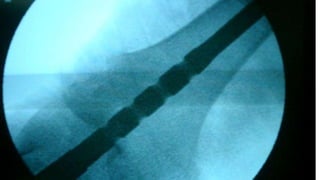

Distal Femur retrograde nailing

Brief steps of distal femoral retrograde nailing of femur